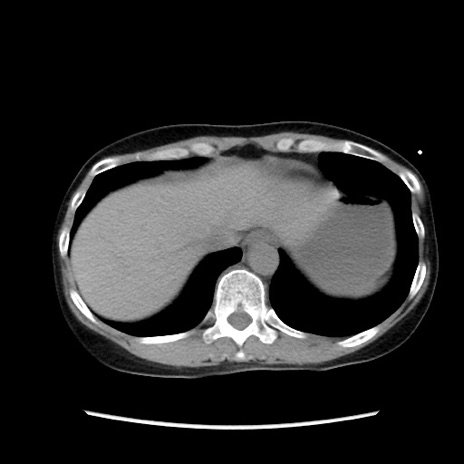

矢状断像